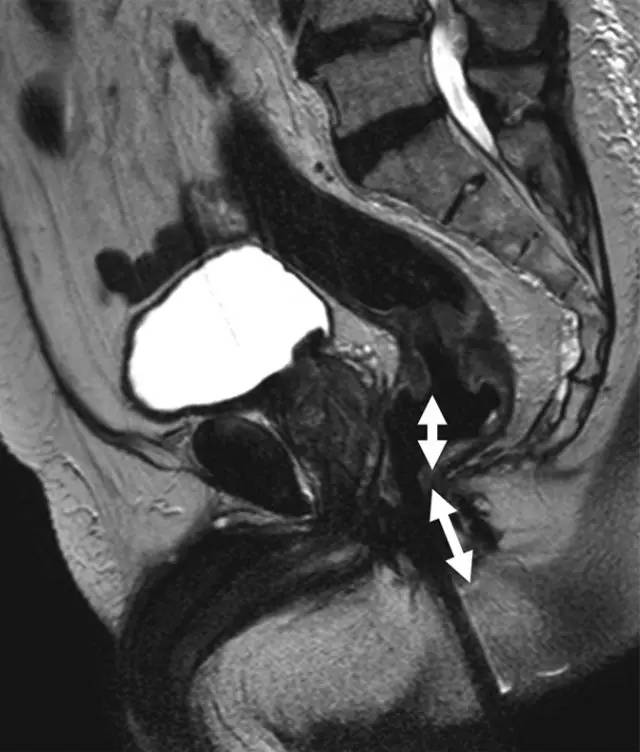

图 1 低位直肠癌患者的矢状 T2 加权图像。箭头显示肿瘤下缘距离肛缘 <5 cm。测量必须以相对直线的方式进行,以便与乙状结肠镜检查相符。

(3)低位:肿瘤的最下缘距离肛缘小于 5 cm。在这个水平上,直肠的直径逐渐变细。直肠系膜筋膜与残留的泌尿生殖隔相融合,是一个致密的筋膜带(男性的 rectoprostatic 筋膜,女性的直肠阴道间隔)。肛管直肠结合部被耻骨直肠韧带向前拉伸。